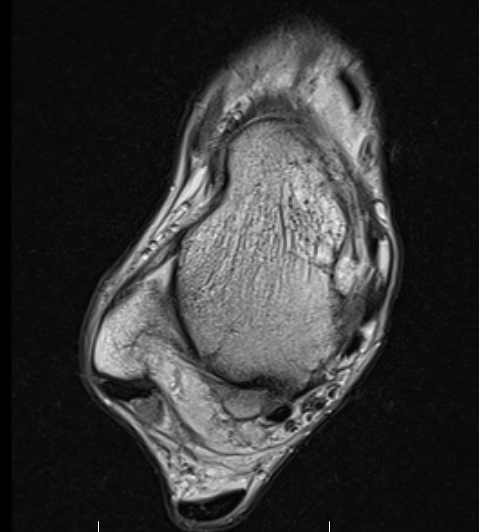

MRI

Findings

- synovitis over posterolateral process talus

- fluid in sheath about FHL

- edema around os trigonum

- edema posterior tibia bone

- thickened posterior capsule

Os trigonum FHL tenosynovitis with posterior ankle joint soft tissue

Stieda's process with ankle joint effusion